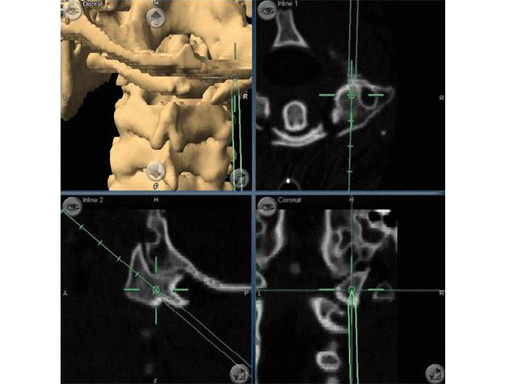

Fig 5ad a Preoperative MRI scan: significant spondylolisthesis in a symptomatic patient.

b Intraoperative x-ray of same patient:

progression to grade II spondylolisthesis in prone position on OR table.

c Minimally invasive surgery allowed decompression, discectomy, instrumentation, and reduction in this patient through two small skin incisions with minimal blood loss.

d Postoperative CT scan: accurate positioning of instrumentation. 3-D-nav allowed for optimization of screw length and diameter given the patients anatomy.